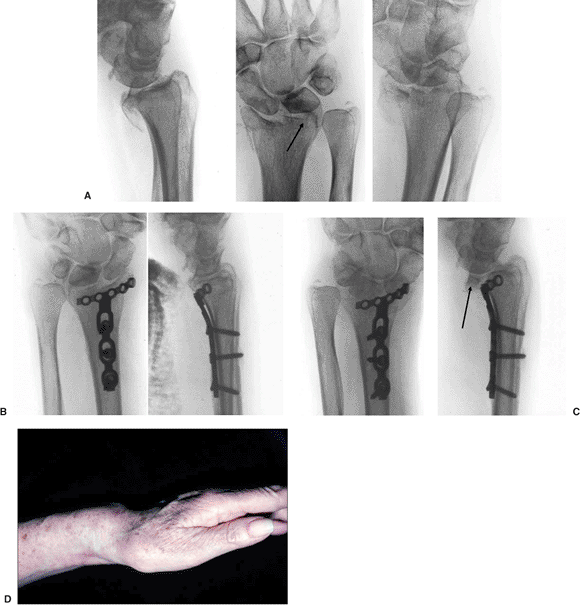

Figure 13.12. Postoperative volar subluxation of the radiocarpal joint. A. Shearing radiocarpal-fracture subluxation with small lunate-facet fracture. B. Immediate postoperative radiographs. C. Subluxation of the radiocarpal joint noted at 2 weeks caused by failure to support lunate-facet fragment. D. Clinical appearance.

|